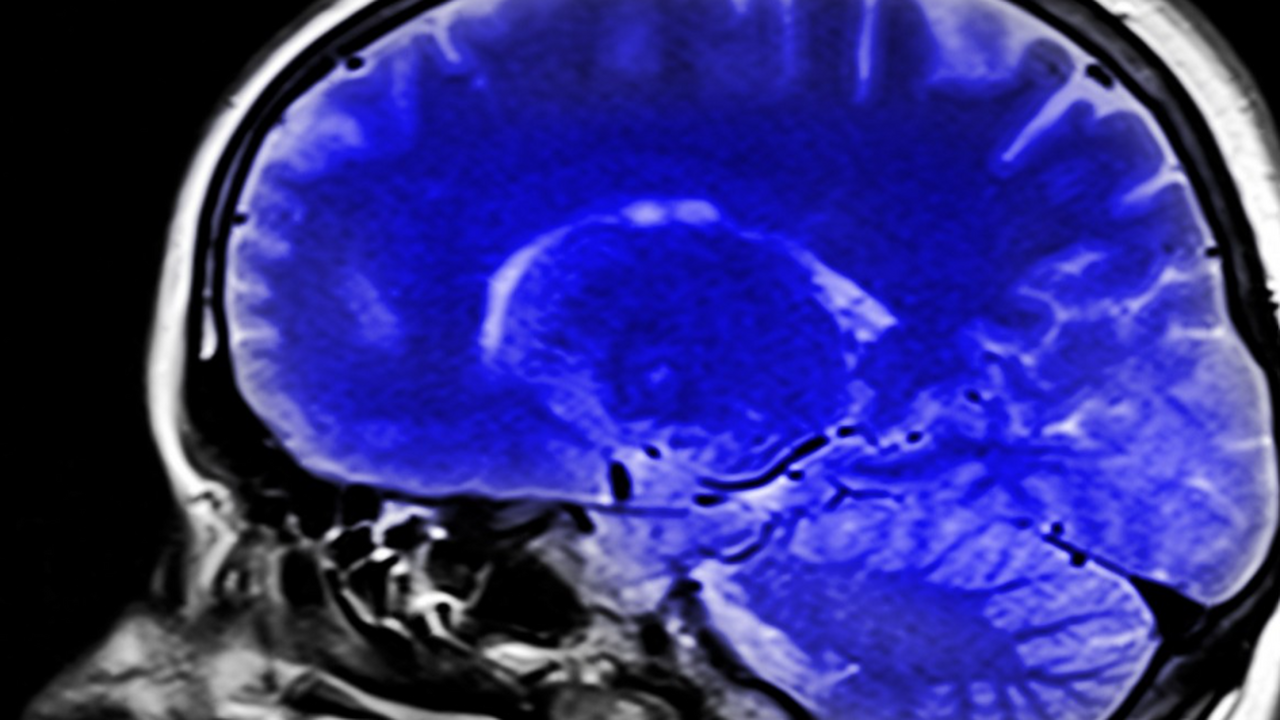

Учёные Массачусетского технологического института (MIT) выяснили, что мозг человека способен «перезагружаться» даже без полноценного сна, пытаясь самостоятельно очиститься от накопленных отходов. Результаты исследования показывают, что при недосыпании организм запускает процесс самоочищения днём, когда внимание временно ослабевает.

Обычно подобное происходит во время глубокого сна: волны спинномозговой жидкости проходят по мозгу, вымывая продукты обмена и токсичные соединения. Однако, как выяснили нейрофизиологи, если человек не высыпается, мозг вынужден проводить такие «чистки» в моменты бодрствования — когда внимание падает и наступают краткие периоды рассеянности.

В исследовании участвовали 26 добровольцев, которых обследовали после полноценного сна и после ночи без отдыха. Учёные зафиксировали, что в состоянии усталости у участников наблюдались волнообразные колебания жидкости, аналогичные ночным процессам очищения. Это свидетельствует о том, что мозг запускает аварийный режим работы, чтобы предотвратить накопление токсинов.

Исследователи отмечают, что данный механизм связан с системой, регулирующей как когнитивную активность, так и физиологические процессы. При хроническом недосыпании мозг вынужден очищаться «на ходу», что может объяснять ощущение кратких провалов внимания и снижение концентрации в течение дня, пишет "Ридлайф.ру".